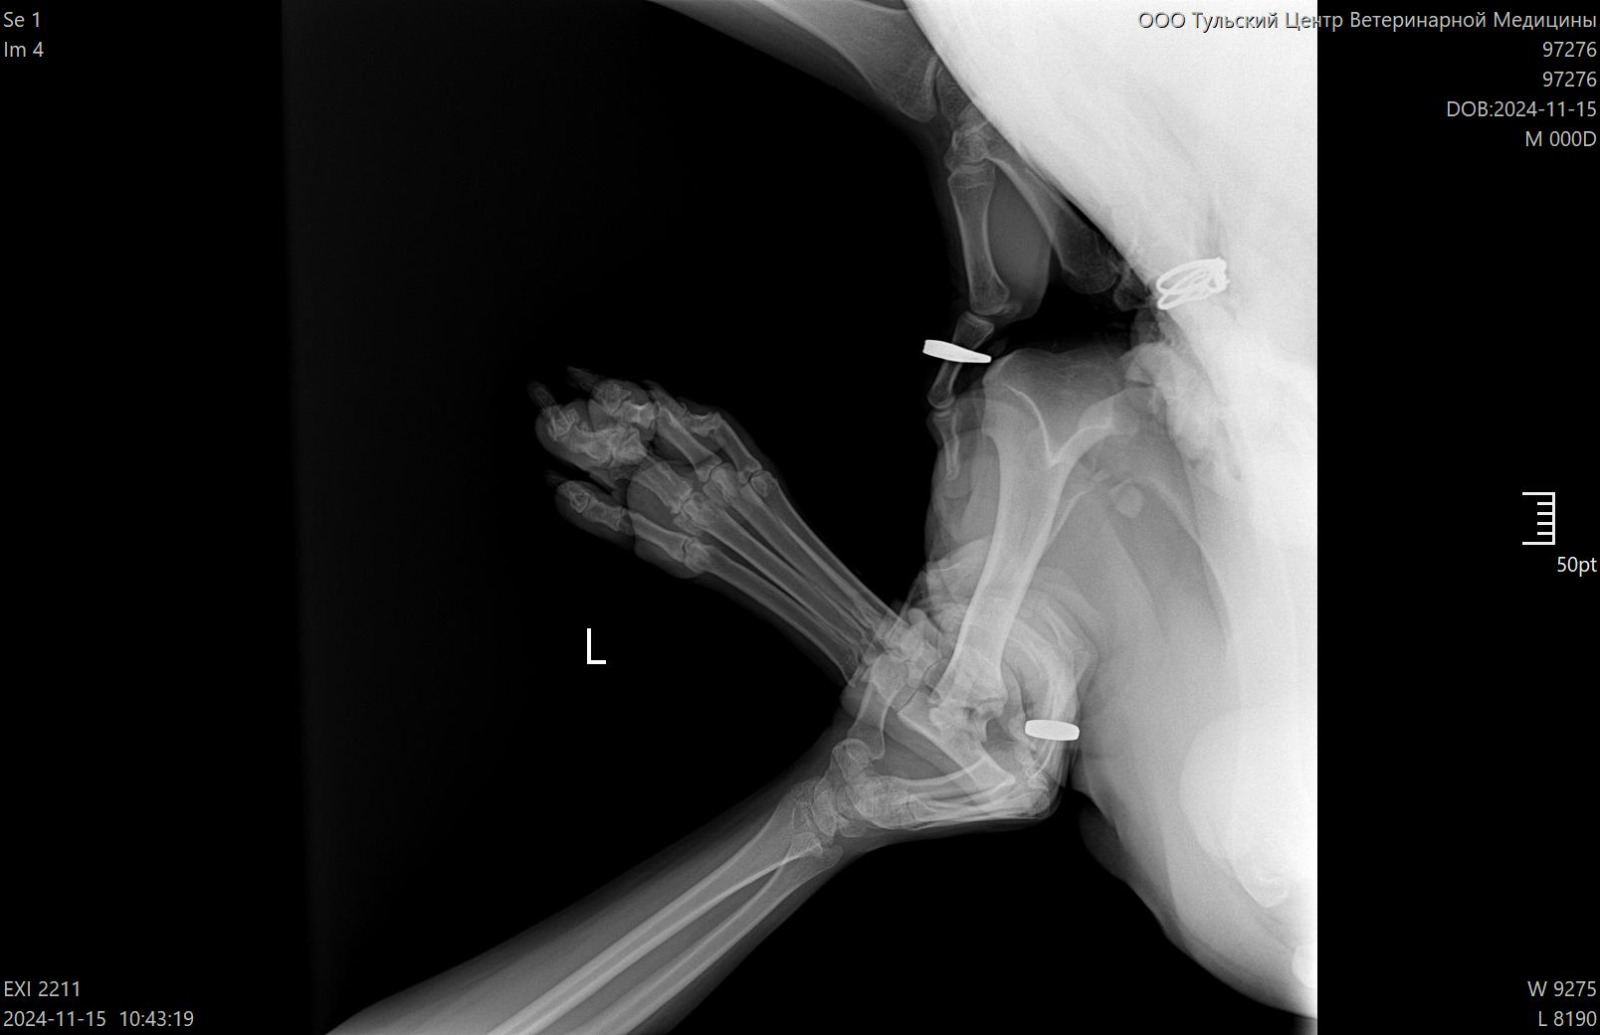

Рентген

Вложения

IMG-20241115-WA0049.jpg

IMG-20241115-WA0050.jpg

IMG-20241115-WA0052.jpg

IMG-20241115-WA0053.jpg

IMG-20241115-WA0051.jpg